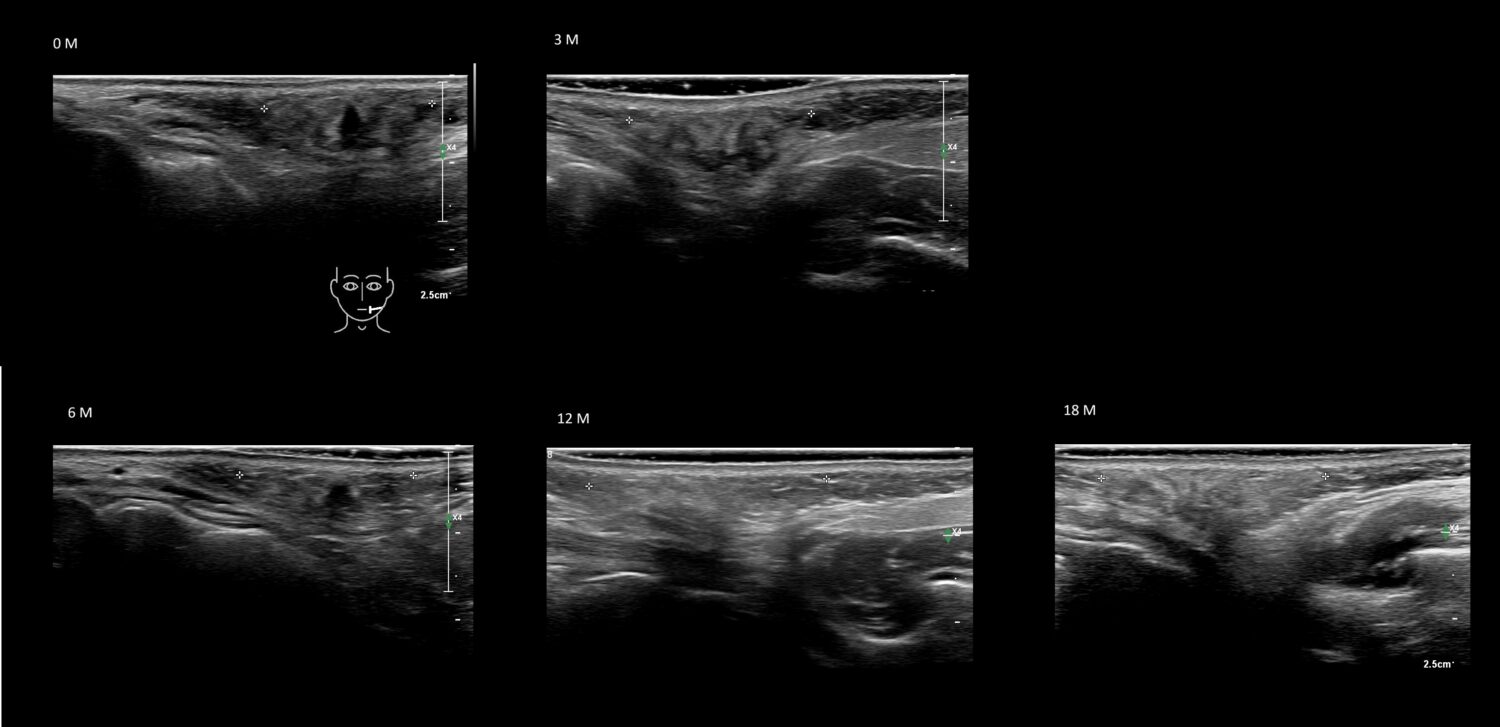

Fillers

Draw in the image on the right where the fillers are located. To check if your answer is correct, please click on the secondary image.